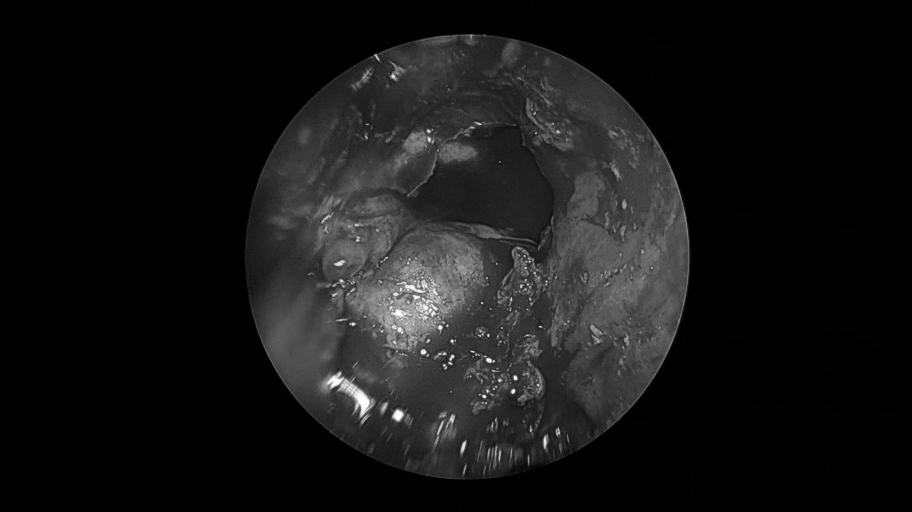

耳内镜检查

双耳鼓膜完整,右侧鼓膜内陷明显,右侧鼓室可见积液